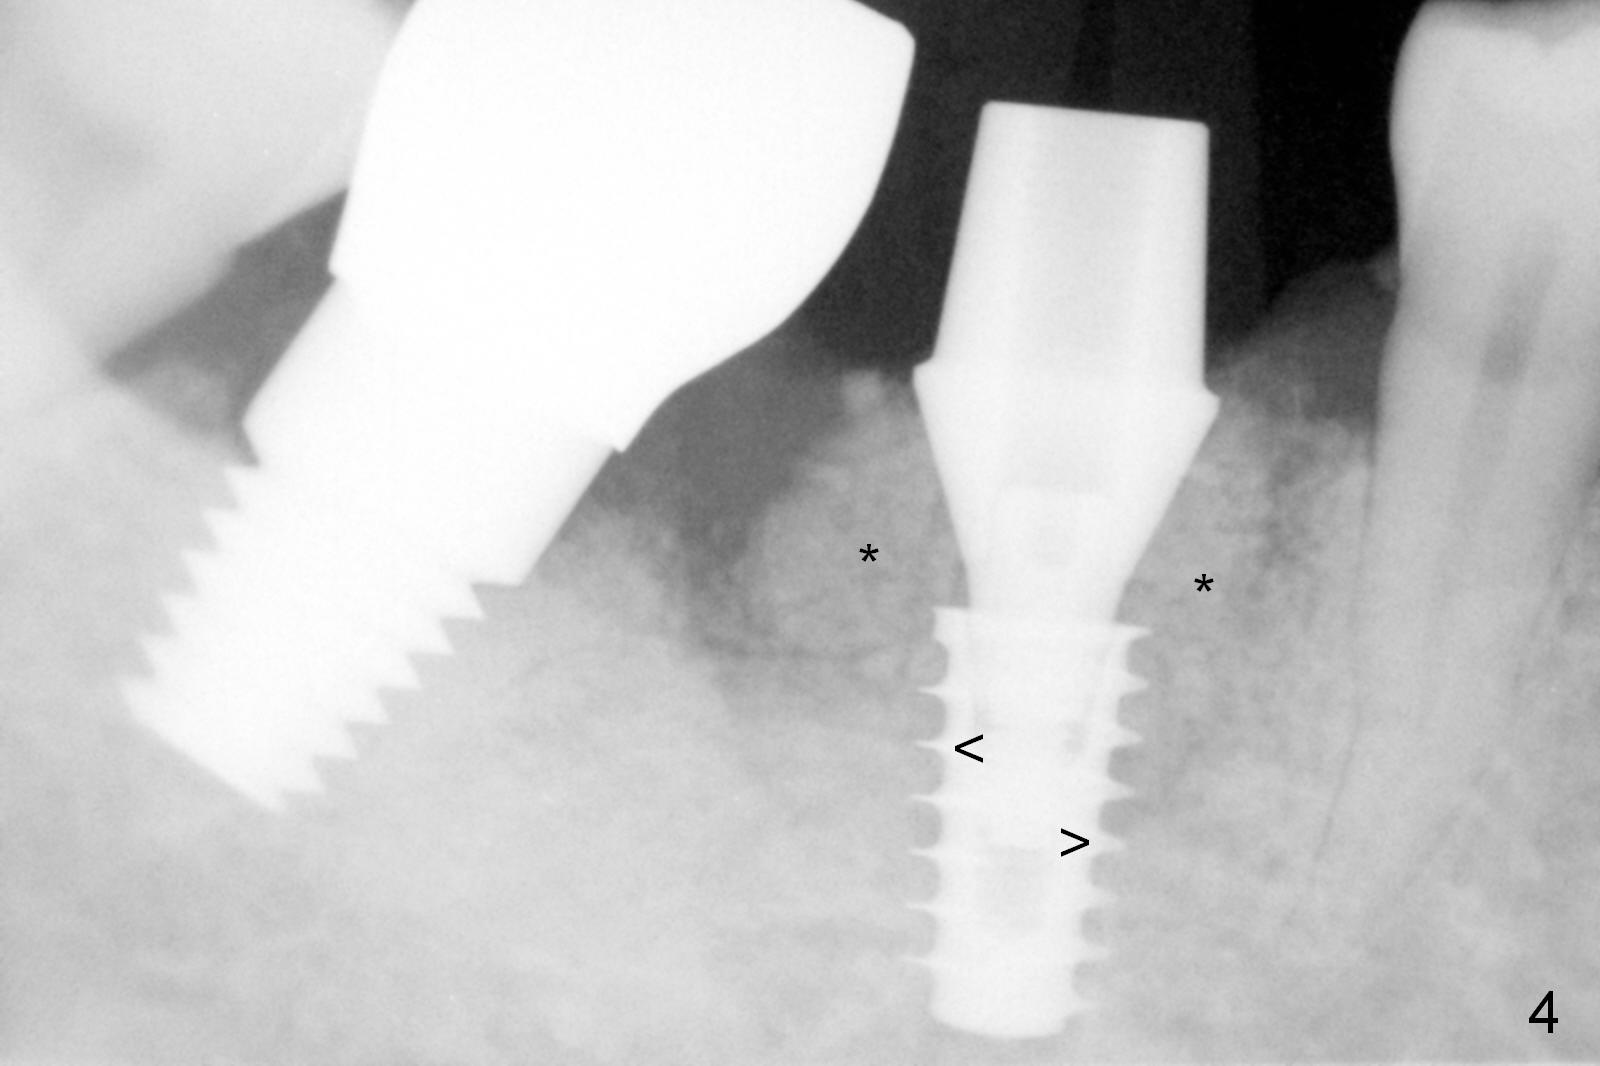

Extraction shows the large distal socket (Fig.1 D) and the thin and low septum (*) of the tooth #30. After Magic Split test confirms hard bone, osteotomy is initiated with 1.6 mm pilot drill with 11 mm stopper (Fig.2); there is 2.7 mm distance to the Inferior Alveolar Canal. Following Marking Bur, a 4.8 mm Magic Drill is used to finish the osteotomy with difficulty because of hard bone and ineffective local anesthesia due to infection. A 5x9 mm "dummy" implant is placed to determine the placement level relative to the distal crest (Fig.3 *). After removal of the dummy implant, an authentic one with the same dimension is placed with packing abundant allograft (.5-1.5 mm) and Osteogen (Fig.4 *); it appears that 4 to 5 threads (fins) of the implant (arrowheads) are engaged to the native bone for primary stability (>40 Ncm). Later more bone graft is placed distally (Fig.5 arrow). With the short implant placed not so deep, there is 6-7 mm clearance from the underlying canal (Fig.6). The patient is doing well 7 days postop (Fig.7). He feels that the provisional is too bulky buccally for the first 2 days postop. The buccal margin will be trimmed in another 2 weeks (dashed line). The patient in fact masticates on the right side postop. By the time he returns for provisional revision 1 months 10 days postop, he has mild pain. There is food entrapment. The provisional and the abutment are slightly loose, whereas the implant is stable with healing socket (Fig.8). A healing abutment is placed. The implant appears unstable nearly 5.5 months postop. The gap between the bone and implant seems to be large (Fig.9). The implant should have been larger and longer for fast healing. A healing screw is used instead. The site heals 10 months postop with an increase in bone density around the implant (Fig.10.) Prior to cementation of the final crown, the abutment is minimally exposed (Fig.11 (6.5x5.7(3) mm)). In fact the abutment screw becomes loose 2 months post cementation (1 year postop); it appears that crown/implant ratio is unfavorable (Fig.12). The implant is slightly placed mesially (cantilever). The patient cannot chew on the left. The tooth #19 is periodontally affected and the tooth #18 is missing. When bone loss is severe, the implant should be as large as possible and preferably tissue-level. The abutment screw is re-loosening 1.5 years post cementation (4 months post #19 socket preservation, Fig.13). The crown/implant ratio at #31 is more favorable than that at #30 (compare black lines). The crown at #31 has large contact area with the tissue-level implant (external), whereas the contact between the abutment and the bone-level implant is much less (internal). To prevent the abutment screw re-loosening (turning) in function, a screw driver (Fig.14 D) will be buried inside the crown/abutment after the screw is retightened. Make sure that the driver is in the middle of the access hole. Section the driver in situ obliquely (Fig.15); flat sectioning allows the driver to turn with the abutment screw in function. After insertion of plumber tape around the sectioned screw driver, use composite to fix the driver in place and seal the access hole (Fig.16). Occlusal check suggests weak link between the abutment and bone-level implant at #30.